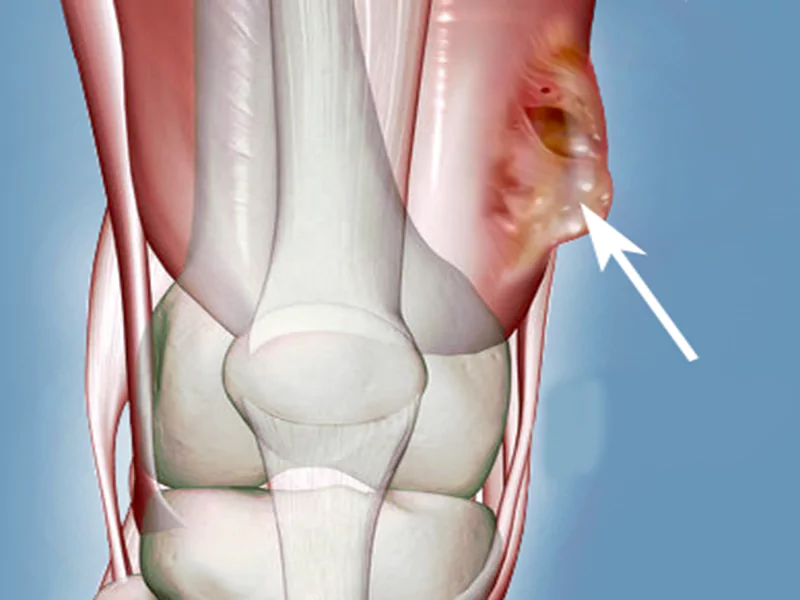

تومورهای عضلانی و اسکلتی به رشد غیرعادی سلولها در بافتهای عضلانی و استخوانی بدن اطلاق میشوند. این تومورها میتوانند خوشخیم یا بدخیم باشند. تومورهای خوشخیم معمولاً به بافتهای اطراف خود نفوذ نمیکنند و رشد آنها کنترل شدهتر است. با این حال، تومورهای بدخیم (سرطان) میتوانند به سرعت رشد کنند و به سایر نقاط بدن سرایت کنند.

تومورهای عضلانی و اسکلتی بیشتر در استخوانها، ماهیچهها، غضروفها و سایر بافتهای حمایتکننده بدن تشکیل میشوند. سارکومها یکی از انواع شایع تومورهای بدخیم هستند که از بافتهای عضلانی و اسکلتی منشأ میگیرند و به سرعت به سایر نقاط بدن گسترش مییابند.

تورم و برجستگی

وجود تورم یا برجستگی غیرعادی در نزدیکی استخوان یا ماهیچه میتواند نشانهای از تومور باشد. این تورم معمولاً به تدریج افزایش مییابد و ممکن است با درد همراه باشد.